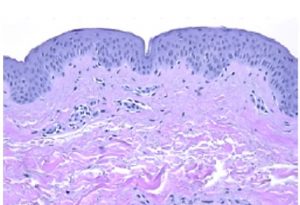

A new tool to visualize the 3D structure of human skin To analyse the effects of cosmetics on human skin, the gold standard remains histological examination. However, this method only allows to observe tissue sections in 2D, whereas natural human skin is organized in a 3D structure. In a recently published study, Syntivia’s Sophie Abadie […]